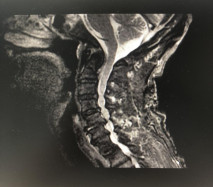

(術(shù)前拍片)

在完善了各項(xiàng)相關(guān)檢查后,張阿伯被診斷為:頸部脊髓損傷,不完全癱瘓及全身多處骨折,我院脊柱科主任戈才華建議其入院并接受頸后路頸椎融合手術(shù)。